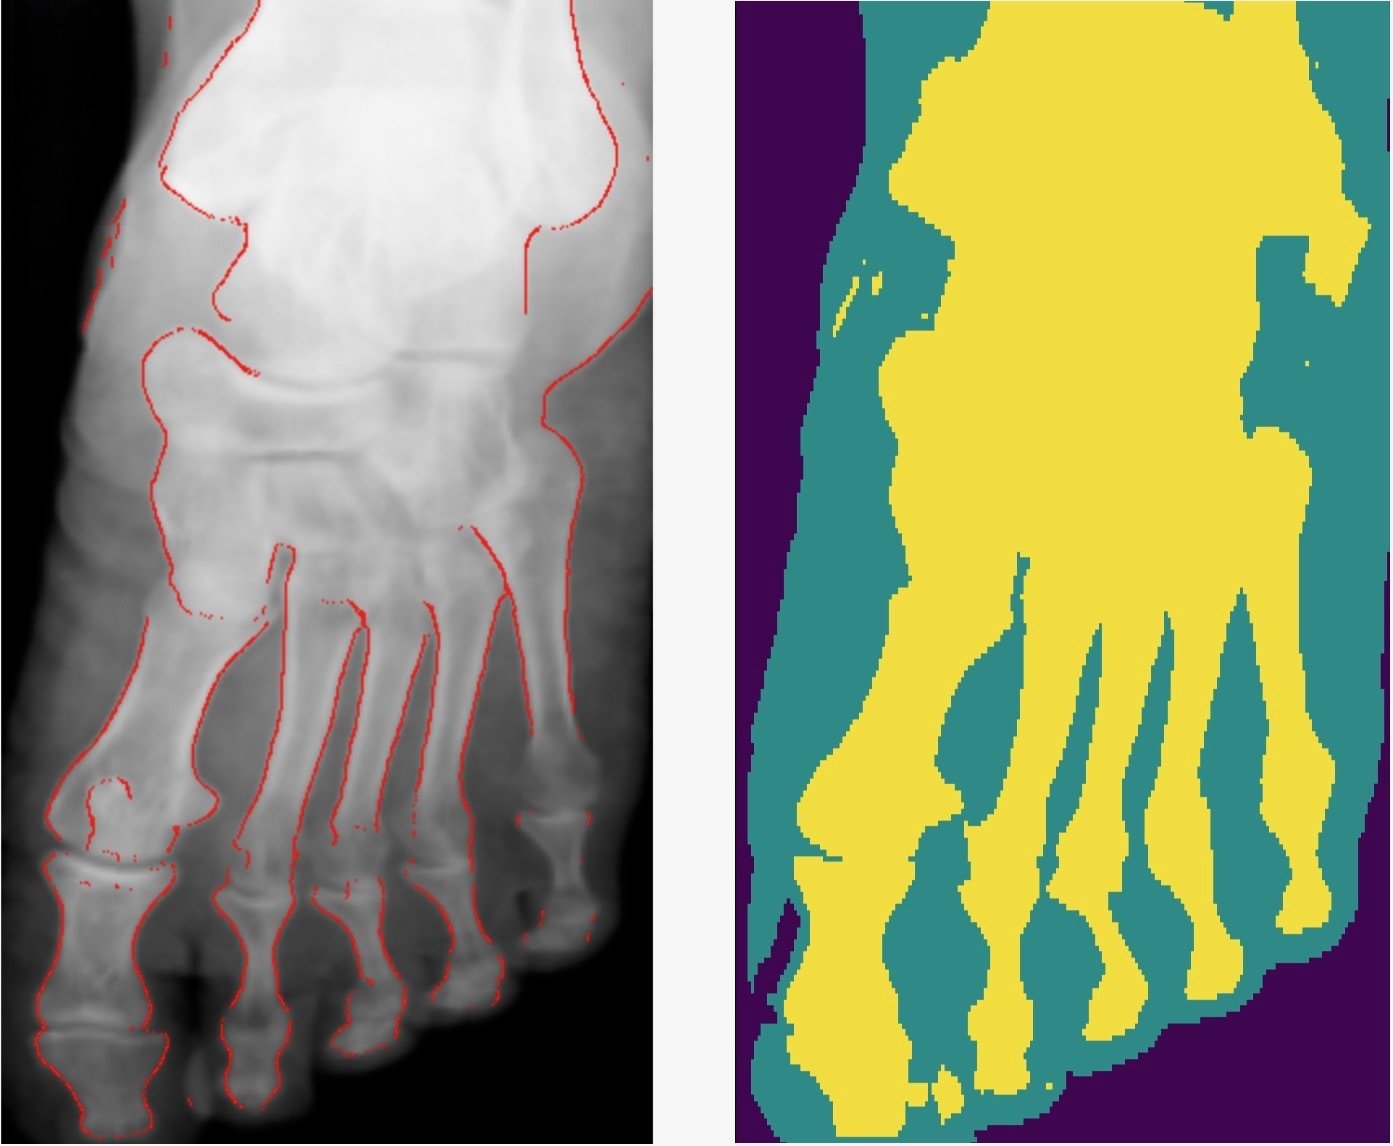

Results

- Generalises well even for unseen categories!

- Overall accuracy on test set: 92%

- Soft tissue TP/FP rate: 82% / 4%

Comparison with other methods

- Smooth connected boundaries.

- Better generalisation to different body parts (we do not have any frontal view of a foot in our dataset).

- More robust to noise.